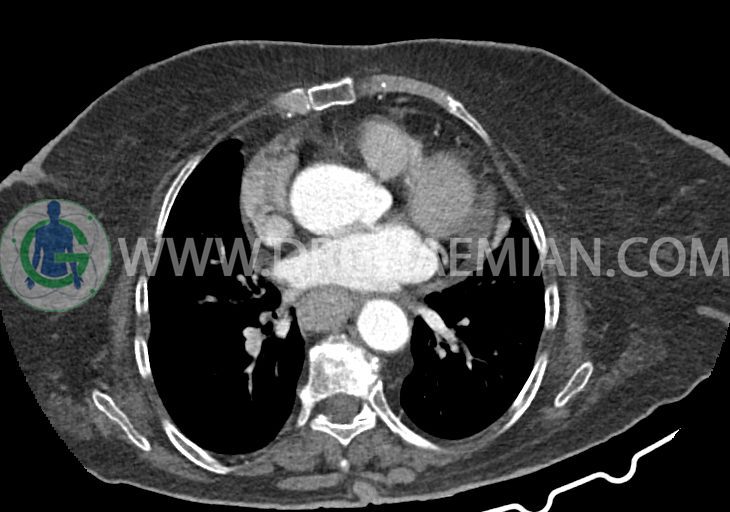

در سی تی اسکن اسپیرال ریه و مدیاستن – شکم و لگن با و بدون کنتراست خوراکی و وریدی (مولتی دیدکتور 16 با مقاطع ظریف و بازسازی های ساژیتال و کرونال):

–کاردیومگالی همراه با pericardial effusion خفیف

–دیلاتاسیون نیمه فوقانی مری توراسیک ناشی از افزایش ضخامت circumferential توده مانند در یک سوم دیستال مری به طول 50mm ، که می تواند مطرح کننده انفیلتراسیون تومورال همراه با تنگی

–آئورت صعودی دیلاته به قطر 38mm